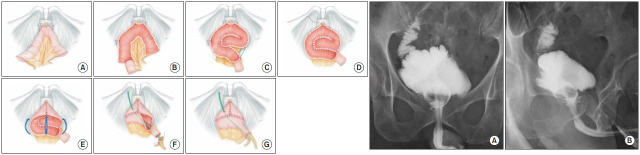

Purpose: We developed a totally intracorporeal neobladder (ICNB) reconstruction technique, termed the Juntendo technique, which features a more spherical configuration by advancing from a hybrid neobladder reconstruction approach. In this report, we describe this ICNB procedure and its outcomes from our initial clinical experience.

Materials and methods: Between March 2022 and December 2024, 20 male patients underwent neobladder reconstruction (hybrid reconstruction in the first 10 and totally intracorporeal reconstruction in the other 10) following robot-assisted radical cystectomy. The reconstruction technique involved detubularization of a 40 cm ileal segment, formation of a spiral posterior wall plate for vertical traction resistance, and circumferential urethroileal anastomosis without a separate enterotomy. The ureters were anastomosed to a 10 cm afferent limb using the Wallace technique. Subsequently, clinical and perioperative outcomes were collected and compared between the hybrid and ICNB groups.

Results: The estimated blood loss or operative time did not significantly differ between the two groups. In both cohorts, no major perioperative complications occurred, and postoperative renal function remained stable. Both groups also achieved high continence rates. At 3-6 months postoperatively, the ICNB group obtained mean values of 174.9 mL for the neobladder volume, 24.2 mL/s for the maximum flow rate, and 10 mL for the post-void residual volume.

Conclusions: ICNB reconstruction using the Juntendo technique is safe and feasible as the hybrid approach while also yielding favorable early functional outcomes. Studies involving larger patient cohorts and longer follow-up periods is warranted for further validation of this technique.